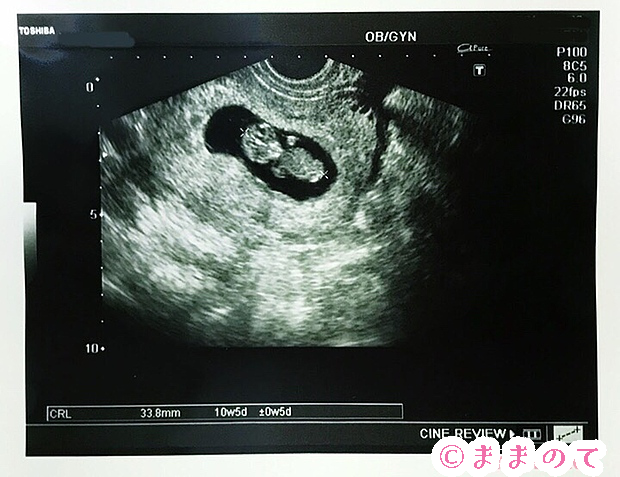

妊婦健診でもらえるエコー写真は、赤ちゃんがお腹の中にいたころの貴重な記録です。紛失や汚れを防ぎ、パパと妊娠経過を共有したり、後で見返したりするときのためにも、アルバムにまとめておきたいですね。

エコー写真は、感熱紙という素材にプリントされています。感熱紙は熱に弱く、時間の経過とともに劣化してしまうことがあります。

メッセージスペースにママのコメントを残しましょう。エコー写真を撮影した日付、胎児の大きさ、ママの腹囲や子宮底長を残すと記録が充実します。パパからのメッセージもあると、赤ちゃんが大きくなったときにうれしく感じるかもしれませんね。